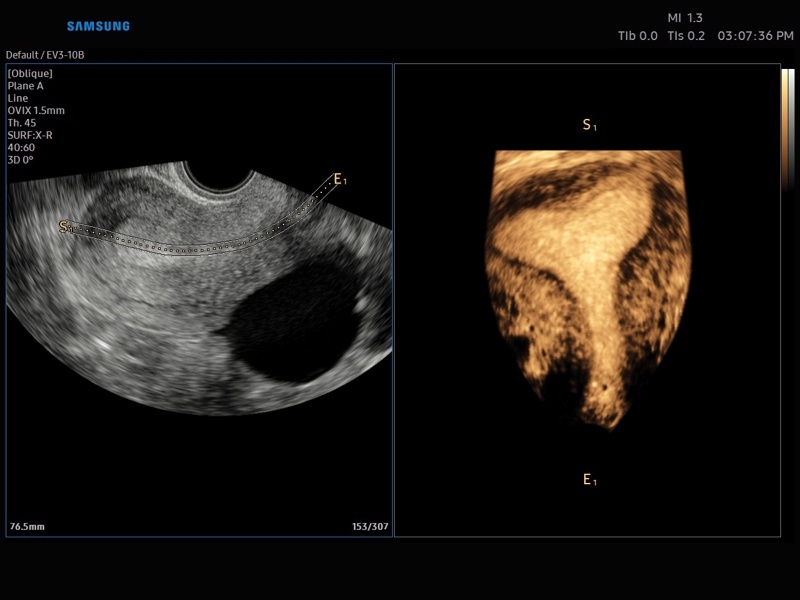

• 3D - трехмерное сканирование объемными датчиками в статическом режиме в серой шкале и восстановление объемной структуры сосудов в режиме цветного / энергетического допплера (необходим Static 3D).

• МодульCrystal Vue- программа реконструкции прозрачного 3D УЗИ, которое получается при одновременном усилении внутренних и наружных структур. Применяется для визуальной оценки состояния плода и матки, помогает лучше идентифицировать мягкие ткани и кости.

• Модуль Crystal Vue Flow- программа реконструкции прозрачного 3D УЗИ, которое получается при одновременном усилении внутренних и наружных структур. Применяется для визуальной оценки состояния плода и матки, помогает лучше идентифицировать мягкие ткани и кости. Так же визуализирует объемный кровоток.

• Система Static 3D - трехмерное сканирование объемными датчиками в статическом режиме в серой шкале и восстановление объемной структуры сосудов в режиме цветного / энергетического допплера).

• СистемаLive 3D- трехмерное сканирование объемными датчиками в реальном масштабе времени (4D).

• OVIX(Oblique View eXtended) - получение фрагмента трехмерного изображения (в виде нескольких полупрозрачных сканов, последовательно наложенных один на другой) в направлении произвольного косого среза трехмерного объекта исследования.